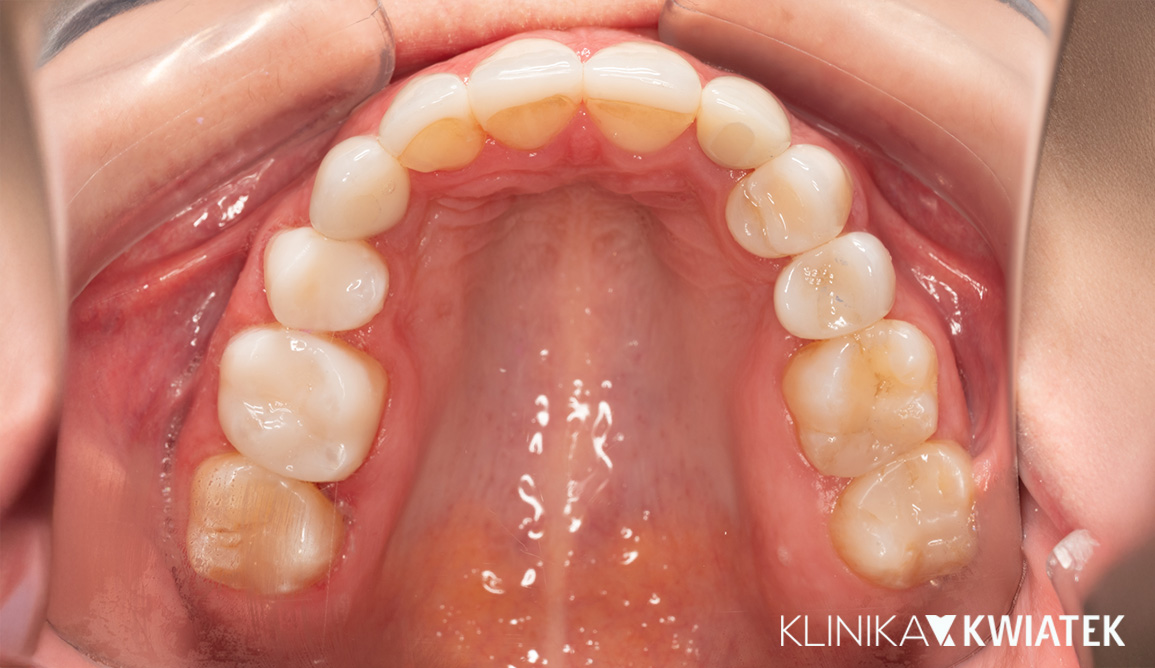

PO

Pacjentka zgłosiła się z powodu napięć mięśniowych, zgrzytania zębami i dolegliwości ze strony stawów skroniowo-żuchwowych. Rozpoczęto terapię od szyny relaksacyjnej i fizjoterapii, a następnie wdrożono leczenie ortodontyczne oraz kompleksową odbudowę protetyczno-estetyczną. Efekt końcowy to nie tylko zdrowy zgryz i brak dolegliwości bólowych, ale także piękny, naturalny uśmiech.